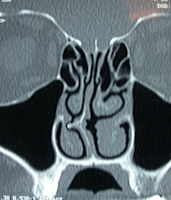

L'étude précise du fonctionnement du nez avant d'envisager une rhinoplastie ou une rhino-septoplastie doit rechercher également une augmentation de volume anormal des cornets inférieurs par simple inflammation chronique ou par rhinite allergique associée. Il y a souvent une hypertrophie du cornet inférieur du côté opposé à la déviation de cloison.

Il faut savoir porter alors l'indication d'une diminution de volume des cornets inférieurs. Il ne se pratique plus de turbinectomie complète accusées d'être à l'origine du syndrome du nez vide, mais plutôt soit une turbinoplastie pour diminution de volume des cornets inférieurs par radiofréquence ou par laser sur fibre souple, celle-ci étant effectuée  dans le même temps que le geste chirurgical. Ce geste associé est simple et rapide et permet de  diminuer le volume excessif de la muqueuse du cornet inférieur en respectant cependant son fonctionnement. Cette intervention sous pratique par voie endoscopique c'est-à-dire en microchirurgie à l'aide d'un système de caméra et d’écran.

Déviations de cloison droite

avec excès de volume du cornet

inférieur gauche